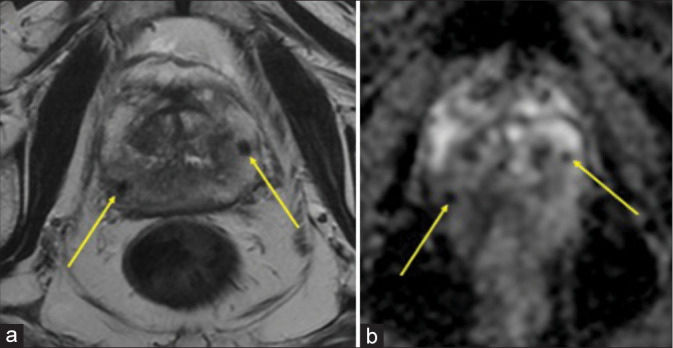

Granulomatous prostatitis (GP) is a rare form of chronic prostatitis with reported incidence of 0.65-1.5%. Radiological features of GP overlap with those of prostate adenocarcinoma. The following magnetic resonance imaging characteristics can suggest the diagnosis in an appropriate clinical setting: Diffuse or focal nodular low T2 signal, high signal on diffusion-weighted imaging with corresponding low apparent diffusion coefficient signal, and post-contrast imaging with lesion enhancement or rim-enhancing in the setting of caseous necrosis or abscess formation. Even with suspicion on imaging, the overlapping imaging features with prostate adenocarcinoma necessitate biopsy for confirmatory diagnosis. Here, we report a case of a 70-year-old man with GP in the setting of prior intravesicle bacillus Calmette-Guérin administration.